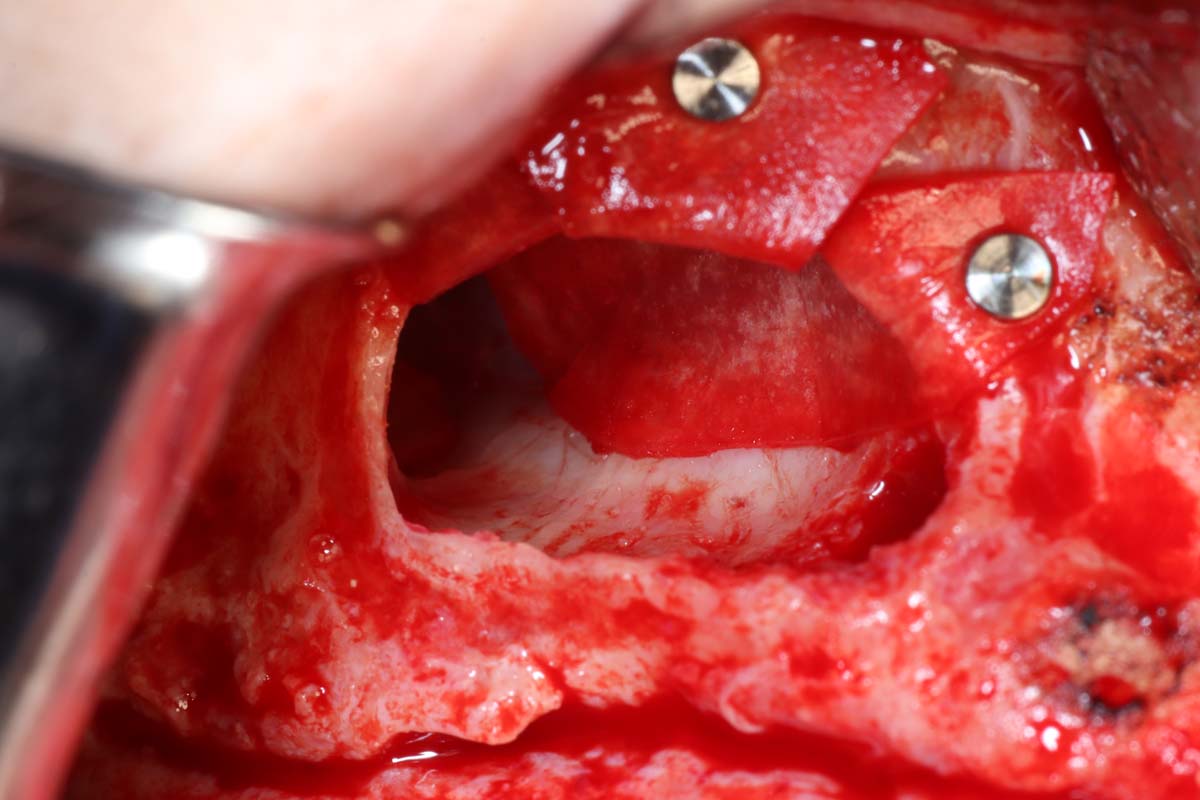

Gain Hands-On Skills and Watch Live Surgery to Master Implant Site Development Techniques

Elevate your skills in implant site development with hands-on practice and live surgical demonstrations. Observe procedures in real time and participate in practical sessions to build confidence in essential techniques, from bone grafting to soft tissue management.

- Indications and step by step surgical protocol for sinus bone grafting – lateral and crestal approach.